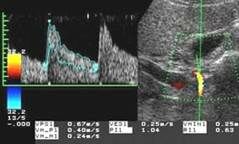

8.Оценка печеночной гемодинамики включает исследование основных сосудов печени - печеночных вен, воротной вены и печеночной артерии, а также их крупных ветвей. Предпочтительно использовать режим ЦДК, позволяющий уточнить не только наличие, но и направление кровотока. Помимо сосудов печени в режиме ультразвуковой ангиографии исследуются круглая связка печени и передняя брюшная стенка - вдоль белой линии живота с использованием линейного датчика, что позволяет более точно выявить наличие кровотока в параумбиликальной вене. ЦДК является высокоинформативным методом в определении обратного (гепатофугального) кровотока в воротной вене и наличия кровотока в порто-кавальных коллатералях. Используя ЦДК, можно быстро определить - является ли визуализируемая трубчатая структура сосудом, оценить наличие и направление кровотока в нем. При ЦДК во внутрипеченочной части воротной вены и в ее ветвях отмечается красный сигнал спектра, соответствующий обычному (гепатопетальному) направлению кровотока при стандартных настройках аппарата. В печеночных венах в норме регистрируется синий сигнал спектра, соответствующий кровотоку от печени, к нижней полой вене и правым отделам сердца.

Определение количественных показателей гемодинамики печени. Больной исследуется в положении лежа на левом боку. Сканирование проводится из доступа через межреберные промежутки (интеркостальный доступ) или из правого подреберья (субкостальный доступ) в зависимости от оптимальной видимости исследуемого сосуда и его хода по отношению к углу инсонации. Задержка дыхания производится больным вне фазы глубокого вдоха или выдоха, что снижает влияние фаз дыхания на характер кровотока в исследуемых сосудах. При определении скоростей кровотока сканирование проводится таким образом, чтобы направление распространения ультразвуковых волн максимально совпадало с продольным ходом сосуда и не превышало 60 градусов по отношению к нему. Величина пробного объема, помещаемого в середину просвета сосуда, составляет приблизительно одну его треть. При измерении таких уголнезависимых величин, как индекс резистентности (RI) и пульсационный индекс (PI), коррекция угла инсонации имеет меньшее значение. При исследовании кровотока во внутрипеченочной части основного ствола воротной вены Nishihara (1994) отметил наилучшие результаты при сканировании из межреберного доступа. Он помещал контрольный объем в основной ствол воротной вены за 1-2 см до ее бифуркации на левую и правую долевые ветви. С учетом данных литературы и своего личного опыта мы считаем указанную выше позицию оптимальной для определения скоростных показателей воротного кровотока (см. рис.).

В норме воротный кровоток имеет типичный венозный спектр, зависящий от фаз дыхания и располагающийся над базовой линией, что соответствует его обычному (гепатопетальному) направлению. Исследование скоростных показателей в основном стволе печеночной артерии проводится в области вертикально направленной части, в точке, наиболее удаленной от бифуркации чревного ствола при сканировании из правого подреберья. В норме скорость кровотока в ней не превышает 60-70 см/сек, RI обычно равен 0,65-0,7.

Визуализация печеночных вен не представляет существенной трудности как из интеркостального, так и из субкостального доступов. При исследовании печеночных вен по методике, предложенной Bolondi (1991), контрольный объем, составлявший 1/3 просвета сосуда, помещается в среднюю печеночную вену на расстоянии 3-6 см от места впадения ее в нижнюю полую вену, что позволяет исключить влияние последней на форму допплеровского спектра. В норме спектр кровотока в печеночных венах трехфазный и зависит от фаз сердечного цикла (см. рис).